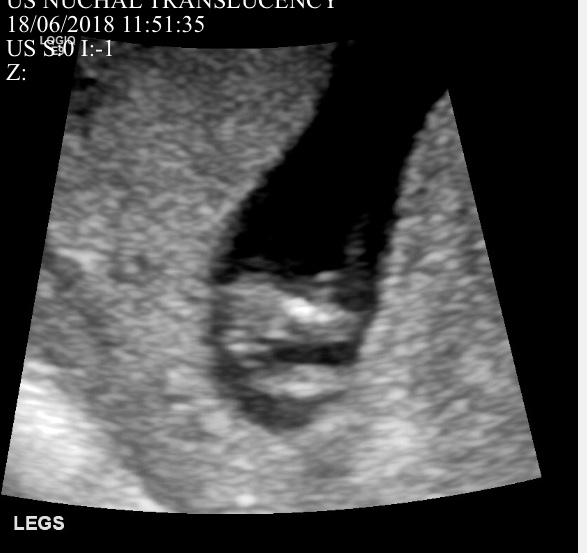

Hi guys. I’m posting 2 profile photos and 2 potty shots from my 12 week scan (measure 12w1d). I am not sure if either of the profile photos show a nub - if so, what are your guesses based on either of the profile photos or the potty shot?

I see 3 lines in the potty shot but the middle line is much longer pointing out. I will update on Friday when I find out but would love some guesses until then. TIA. Attachment 39791Attachment 39792Attachment 39793Attachment 39794